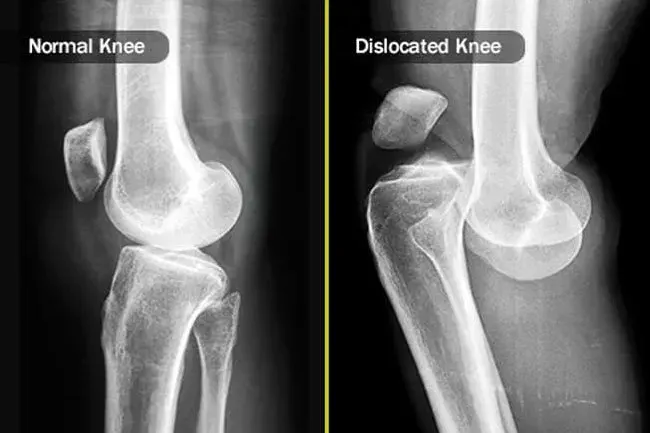

Dislokationer og brud

Hvis dit knæ gør ondt efter et støddæk eller fald, har du måske brudt en af ​​knoglerne, der mødes der oppe - låret Shin og Knecap - eller flyttet en malplaceret. Gå til skadestuen eller se en læge så hurtigt som muligt. Nogle gange sker der brodder brud langsommere med små revner i enderne af benbenene. Dette kan ske, når du er begyndt at bruge dit knæ mere.

1. Stocktrek -billeder / videnskabskilde